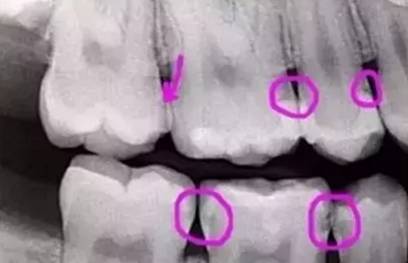

先放几张图,让你们涨涨姿势,不拍片根本不知道你的牙齿长得会有多奇葩!

下图圈出来的地方或多或少都有点龋齿,但是有些你并不能看见。这些龋齿还浅不会让你有什么感觉,顶多吃东西塞牙,和冷水敏感而已。

每颗牙都有所龋坏

暗的部位说明龋齿已经非常严重了!

龋坏接近牙髓了